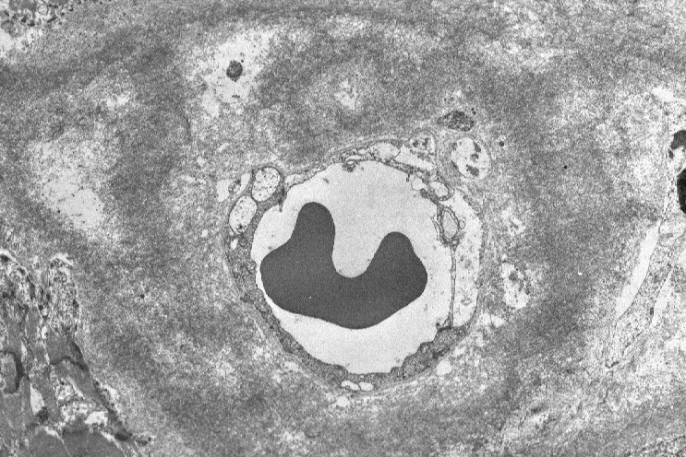

4. Electron microscopic investigation of the myocardium reveals the deposition of electron-dense substance, which is composed of randomly oriented, non-branching, less-than-10 nm diameter fibrils, in the perivascular spaces ([jpg.74KB]) and around the isolated myocytes. The analysis of the renal cortex, too, reveals focal deposition of the fibrils of the similar characteristics in the mesangial matrix that is not necessarily expanding. The glomerular basement membrane is not thickened, i.e., 250 nm, and free of electron-dense deposits. The slit membrane between the foot processes of the podocytes is confirmed to be intact, the foot process fusion not being observed.